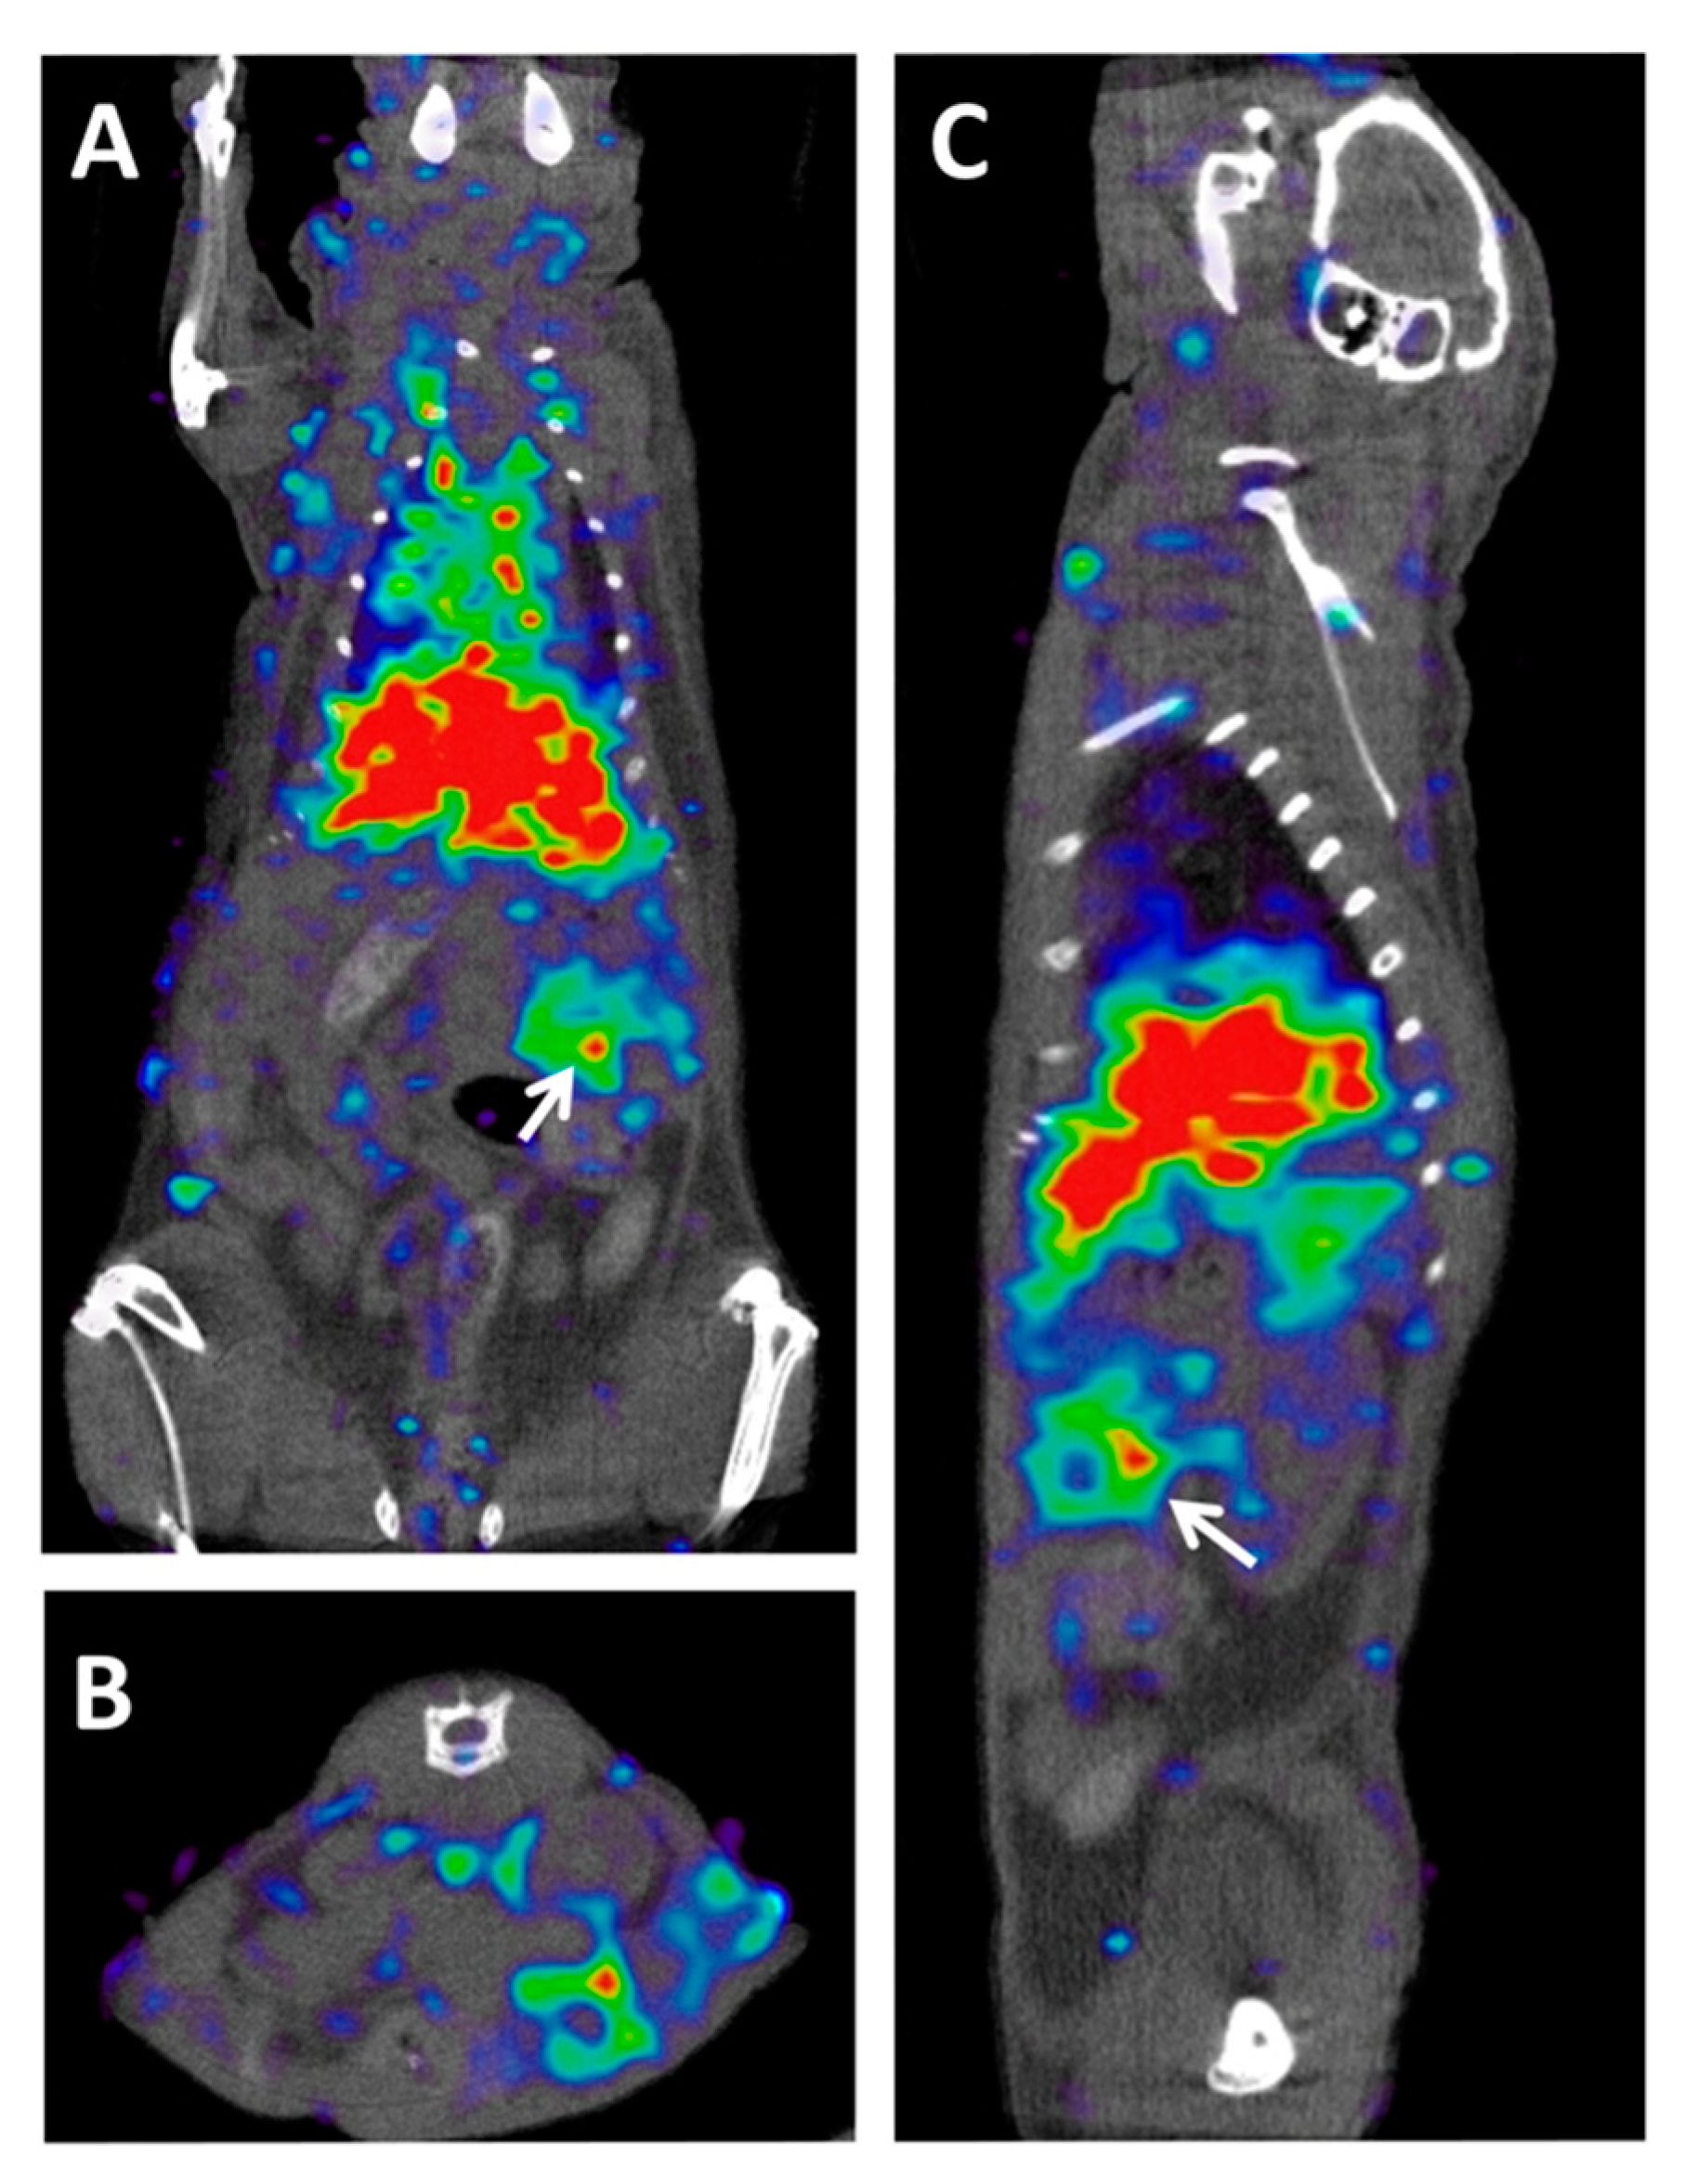

2.4. PET Hybrid Imaging

3.2. The Current Status of Immuno-PET in PDAC